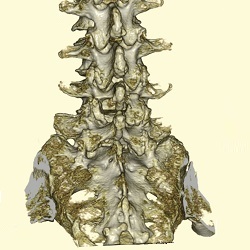

脊柱変形(側弯、後弯症)

脊柱側弯症や腰椎後弯症(腰曲がり)は姿勢異常だけでなく、頑固な腰痛、下肢の痛み、しびれ、さらには食欲の低下、胃腸障害などを引き起こすこともあります。このような場合には脊柱変形矯正術を行います。以前はご高齢の患者様にとってはかなり負担の大きな手術でしたが、側方進入腰椎前方固定術(OLIFやXLIF)の導入により、安全に行えば手術時間や出血量を大幅に減らすことが出来るようになりました。

側方進入前方固定術

側方進入前方固定術とは、体の側方から手術を行う方法です。従来の前方固定術をさらに低侵襲にした方法です。

脊柱変形に対する矯正固定術

術前

術後

側弯が矯正されています。

術前

術後

側弯が矯正されています。